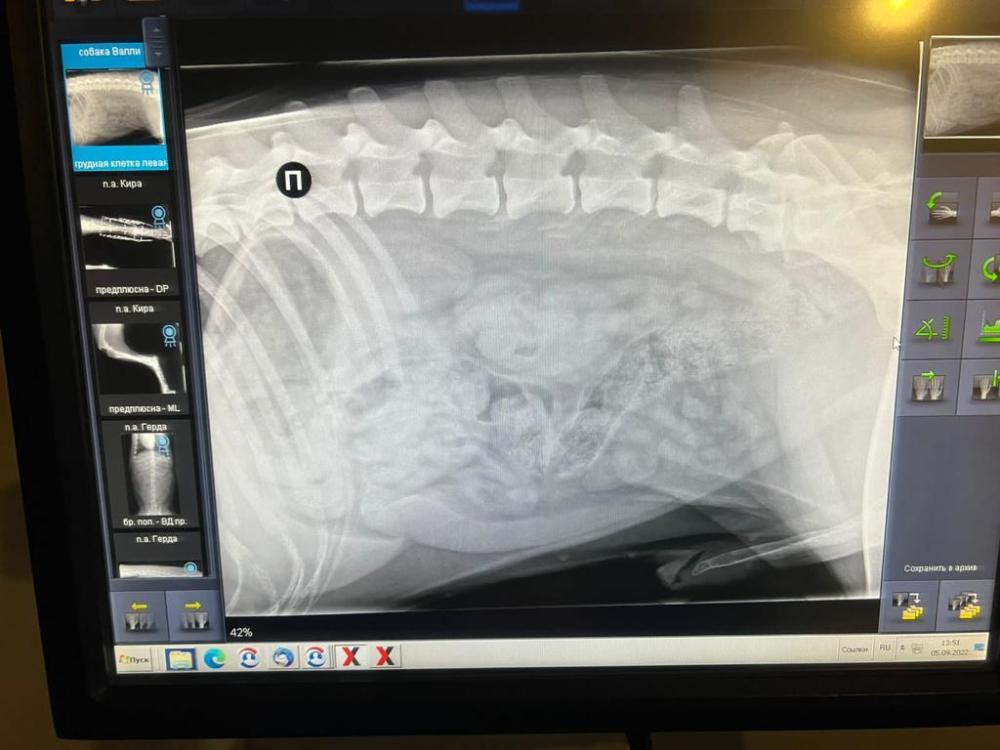

Шилопопый шоколад Валико наконец посетил доктора УЗИ и сдал анализы. Ура! Ничего по картине не ухудшилось, что не может не радовать!

Камушки в мочевом остались такими же, не растут, ЖКТ без изменений, то место, где проблема, не  изменяется, не ухудшается картина. Возможно, что он с этим дефектом вообще родился и нужно сидеть на легких для переваривания кормов а-ля гастро.

У Алексеевой проконсультировались, она считает,  что лучше все также сидеть на Уринари, потому как надо контролировать камушки и не допускать их рост. Сейчас они совсем малы и не приносят проблем, с такими можно жить всю жизнь. Но если будет рост и проморгать  - придется лезть вытаскивать.

13200руб УЗИ, рентген, все анализы